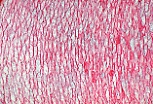

朗格汉斯细胞是抗原呈递树突状细胞,位于棘层。

常规染色的组织切片中无法与邻近角质形成细胞区分,但可通过特殊的组化技术(如本图的ATP酶染色)或免疫组化技术在光镜(M.O.)下检测到, 此时可显示其星状(树突状)形态。 |